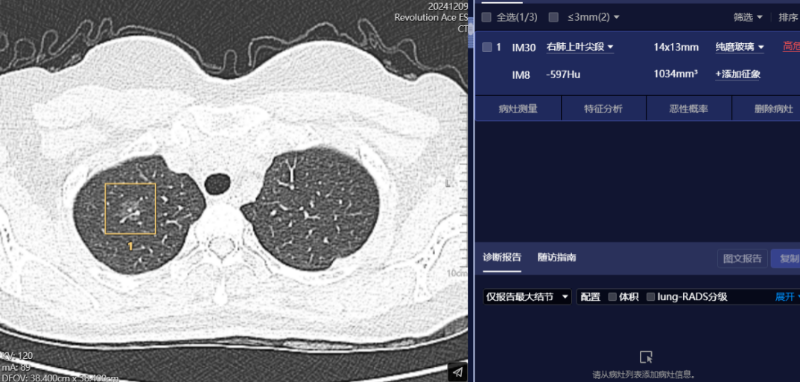

肺部结节筛查

肺癌是世界范围内患病率和病死率最高的恶性肿瘤之一。如果能在早期阶段(尤其是Ⅰ期)进行手术切除,可显著改善肺癌患者预后。然而,癌前病变、微浸润性或浸润性肿瘤常表现为磨玻璃结节,密度浅淡,传统的医师肉眼诊断漏诊率高。

AI人工智能凭借其准确的算法模型,能在短时间内检出,能对其进行定位定性、生长预测、预测恶性病变的病理分级及转移和预后等。在坚持定期CT扫描的情况下,可以早期发现肺病变,提高治愈率。通常情况下,一位患者的常规胸部CT薄层图像超过300幅,高年资影像诊断医师肉眼观察肺窗需超过5-10分钟,而AI在几秒内即可对CT图像进行自动识别、自动定位结节所在的影像层面与解剖位置,自动测量病灶结节大小、CT值等关键参数,并自动对结节类型进行分型,自动预测结节病灶的恶性概率。